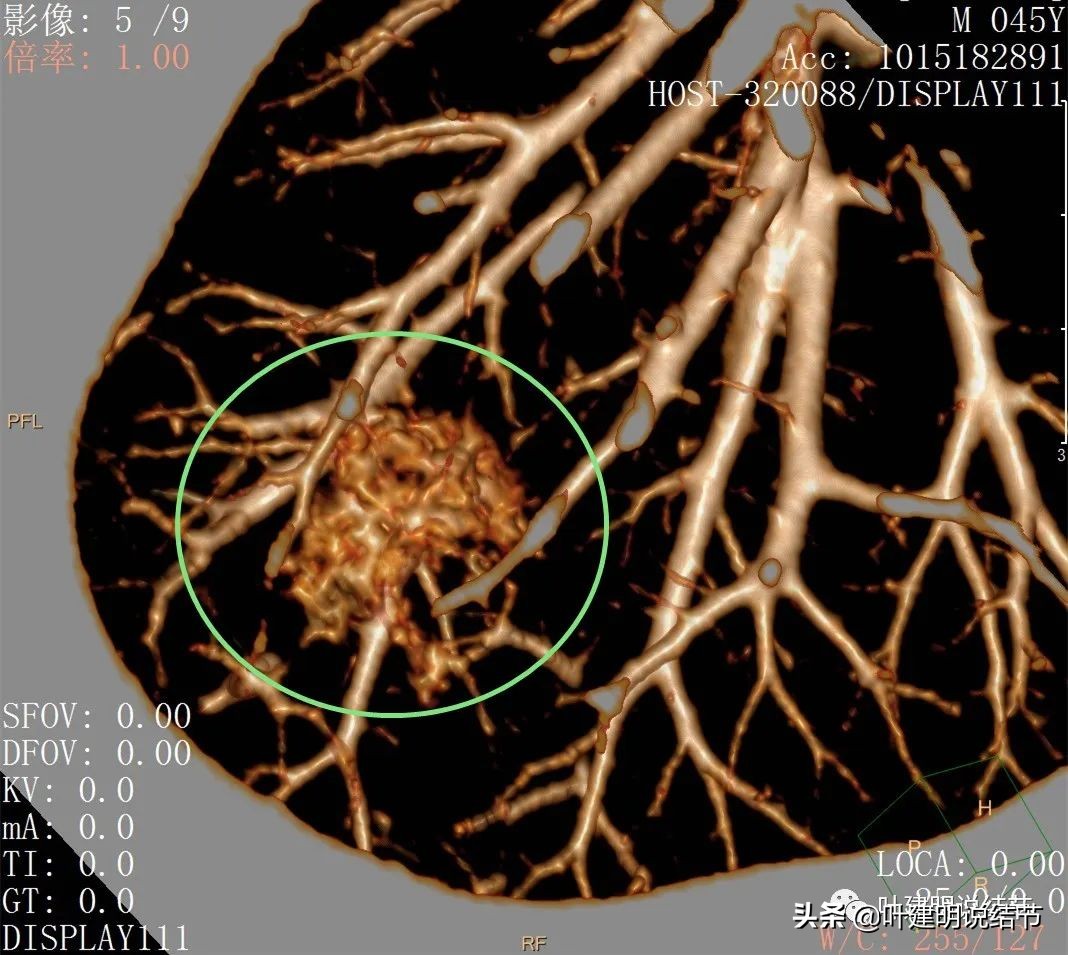

后处理影像:

血管征明显,从不同角度与方向进入,并在病灶内增粗

病灶内部血管联通以及偏高密度成分,血管进入并分支

上图这个层面非常不舒服:病灶多处血管进入,并图像下方这个区域是较粗血管穿过病灶区域,而且有血管被病灶侵蚀的感觉,分支发出进入病灶后也未见穿出;管壁也不平整;病灶整体轮廓很清楚,瘤肺边界也清;病灶内部密度不均杂乱;有分叶与毛刺样征。感觉是较为典型的恶性影像。

上图也是多处血管进入,整体轮廓清,内部密度不均。唯一不是很符合恶性的是病灶密度不够密实,显得有点散

到这个层面是更为典型的恶性影像特征:病灶表面分叶不平整(砖色箭头);多支血管进入(桔色箭头);病灶轮廓很清(红色箭头)。而且磨玻璃成分明显,密度杂乱不均,内部有偏实性密度。

三维重建看病灶整体还是类圆形的,只是有的方向延伸出去而已,与血管关系密切。